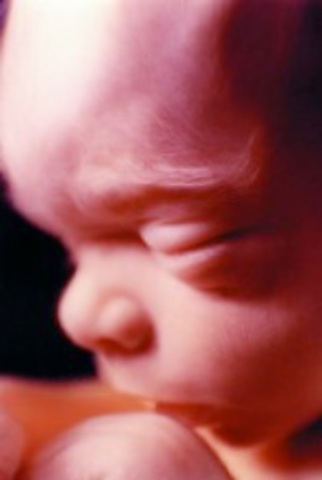

El feto mide casi 11 cm y pesa un poco más de 50 g. Su cabeza mide 3,5 cm de diámetro, ya puede moverla, lo mismo ocurre con sus brazos, manos y piernas. También es capaz de mover los dedos, que ahora sí están ya completamente separados.

Su boca se cierra y se abre y se empiezan a elaborar los pigmentos de la piel.